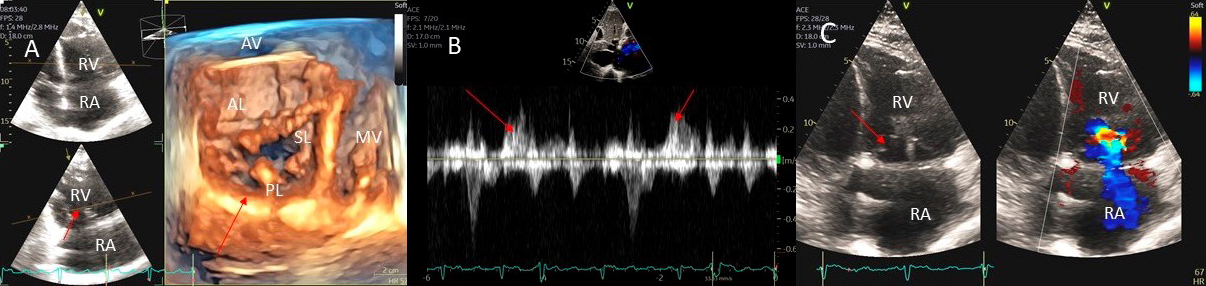

Examples of valvular injury directly from implantable cardioverter-defibrillator lead placement (Fig. 5A–C) or a permanent pacemaker (Fig. 6A–C) or endomyocardial biopsy in cardiac transplant recipients (Fig. 7A,B) are shown.

Fig. 5.Tricuspid regurgitation induced by pacemaker lead impingement. (A) 3D transthoracic echo showing and dilated RV, RA and anterior leaflet impingement by the device lead (red arrows). (B) Inspiratory systolic hepatic flow reversal (red arrows), which suggests severe TR. (C) Apical four chamber view showed severe tricuspid regurgitation. RA, right atrium; RV, right ventricle; AV, aortic valve; AL, anterior leaflet; PL, posterior leaflet; SL, septal leaflet; MV, mitral valve.

Fig. 6.Tricuspid regurgitation induced by pacemaker lead valve perforation. (A) Transthoracic 2D 4 chamber view showing pacemaker lead going through the TV leaflet (white arrow) and causing TR. (B) 3D enface view of the TV from the right atrial perspective showing the pacemaker lead going through the margin of the septal leaflet (SL) of the TV (white arrow). (C) 3D color Doppler view of the TV from the atrial perspective showing origin of TR at the site of leaflet perforation. MV, mitral valve; AV, aortic valve; PL, posterior leaflet; AL, anterior leaflet

Fig. 7.Tricuspid regurgitation following endomyocardial biopsy. (A) Flail tricuspid valve leaflet that occurred as a complication of an endomyocardial biopsy. Apical 4 chamber view showed flail septal leaflet (SL, septal leaflet; AL, anterior leaflet). (B) Color-flow Doppler imaging. Eccentric, anteriorly directed jet of tricuspid regurgitation (SL, septal leaflet of tricuspid valve; AL, anterior leaflet of tricuspid valve).